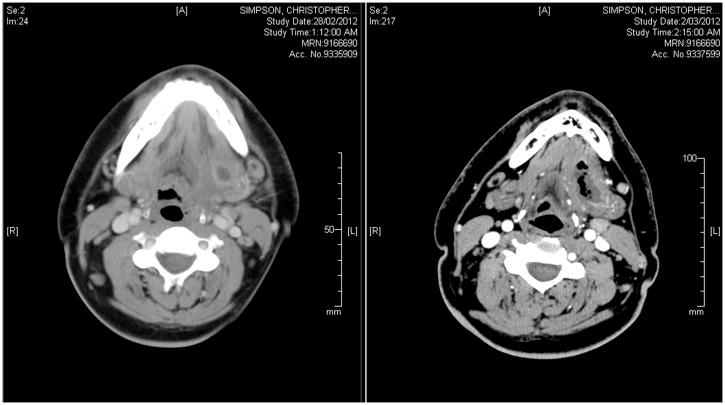

A rare case of submandibular abscess complicated by stroke.

https://cdn.ncbi.nlm.nih.gov/pmc/blobs/921c/3899733/6f1c0853e8f4/10.1177_2042533313505513-fig1.jpg